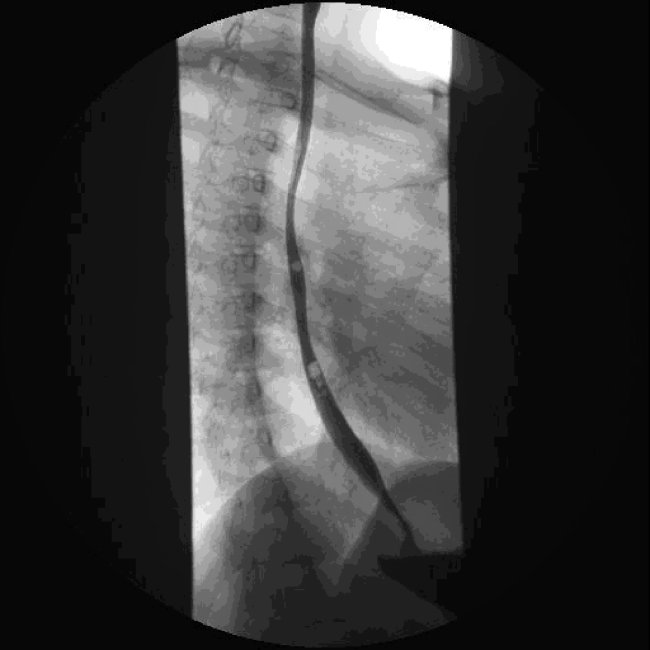

A. ha eseguito un pasto baritato che ha

evidenziato un esofago di calibro costantemente ridotto, con un

restringimento a livello del tratto superiore, scarsa peristalsi e

clearance rallentata (Figura

1).

Fig 1: il transito esofageo di Alessio